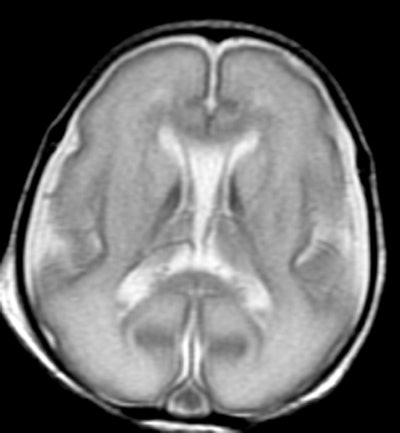

While some white-matter damage is readily apparent on MRI, the current study uses MR spectroscopy to investigate the differences on a microscopic level.

The researchers compared the concentrations of certain chemicals associated with mature white matter and gray matter in 51 full-term and 30 preterm infants. Subjects had normal structural MRI findings, but MR spectroscopy showed significant differences in the biochemical maturation of white matter between term and preterm infants.

The findings suggest there is a disruption in the timing and synchronization of white- and gray-matter maturation. In the premature infants, white-matter development had an early start and was out of sync with gray-matter development, Blüml noted.